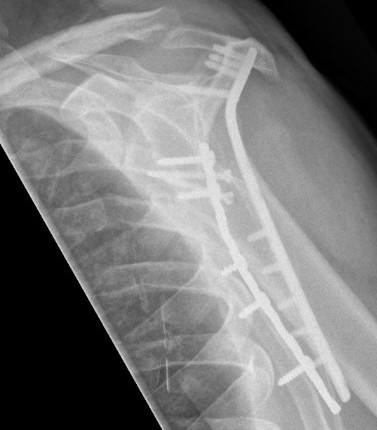

Operative Management

Surgical approach

Judet - detach deltoid and lateral reflection of infraspinatus muscle

Modified Judet - elevate deltoid, use interval between infraspinatus and teres minor

Brodsky lateral column approach - lateral incision, elevate deltoid, use interval between infraspinatus and teres minor

AO surgical foundation posterior approach to surgical body

![]() |